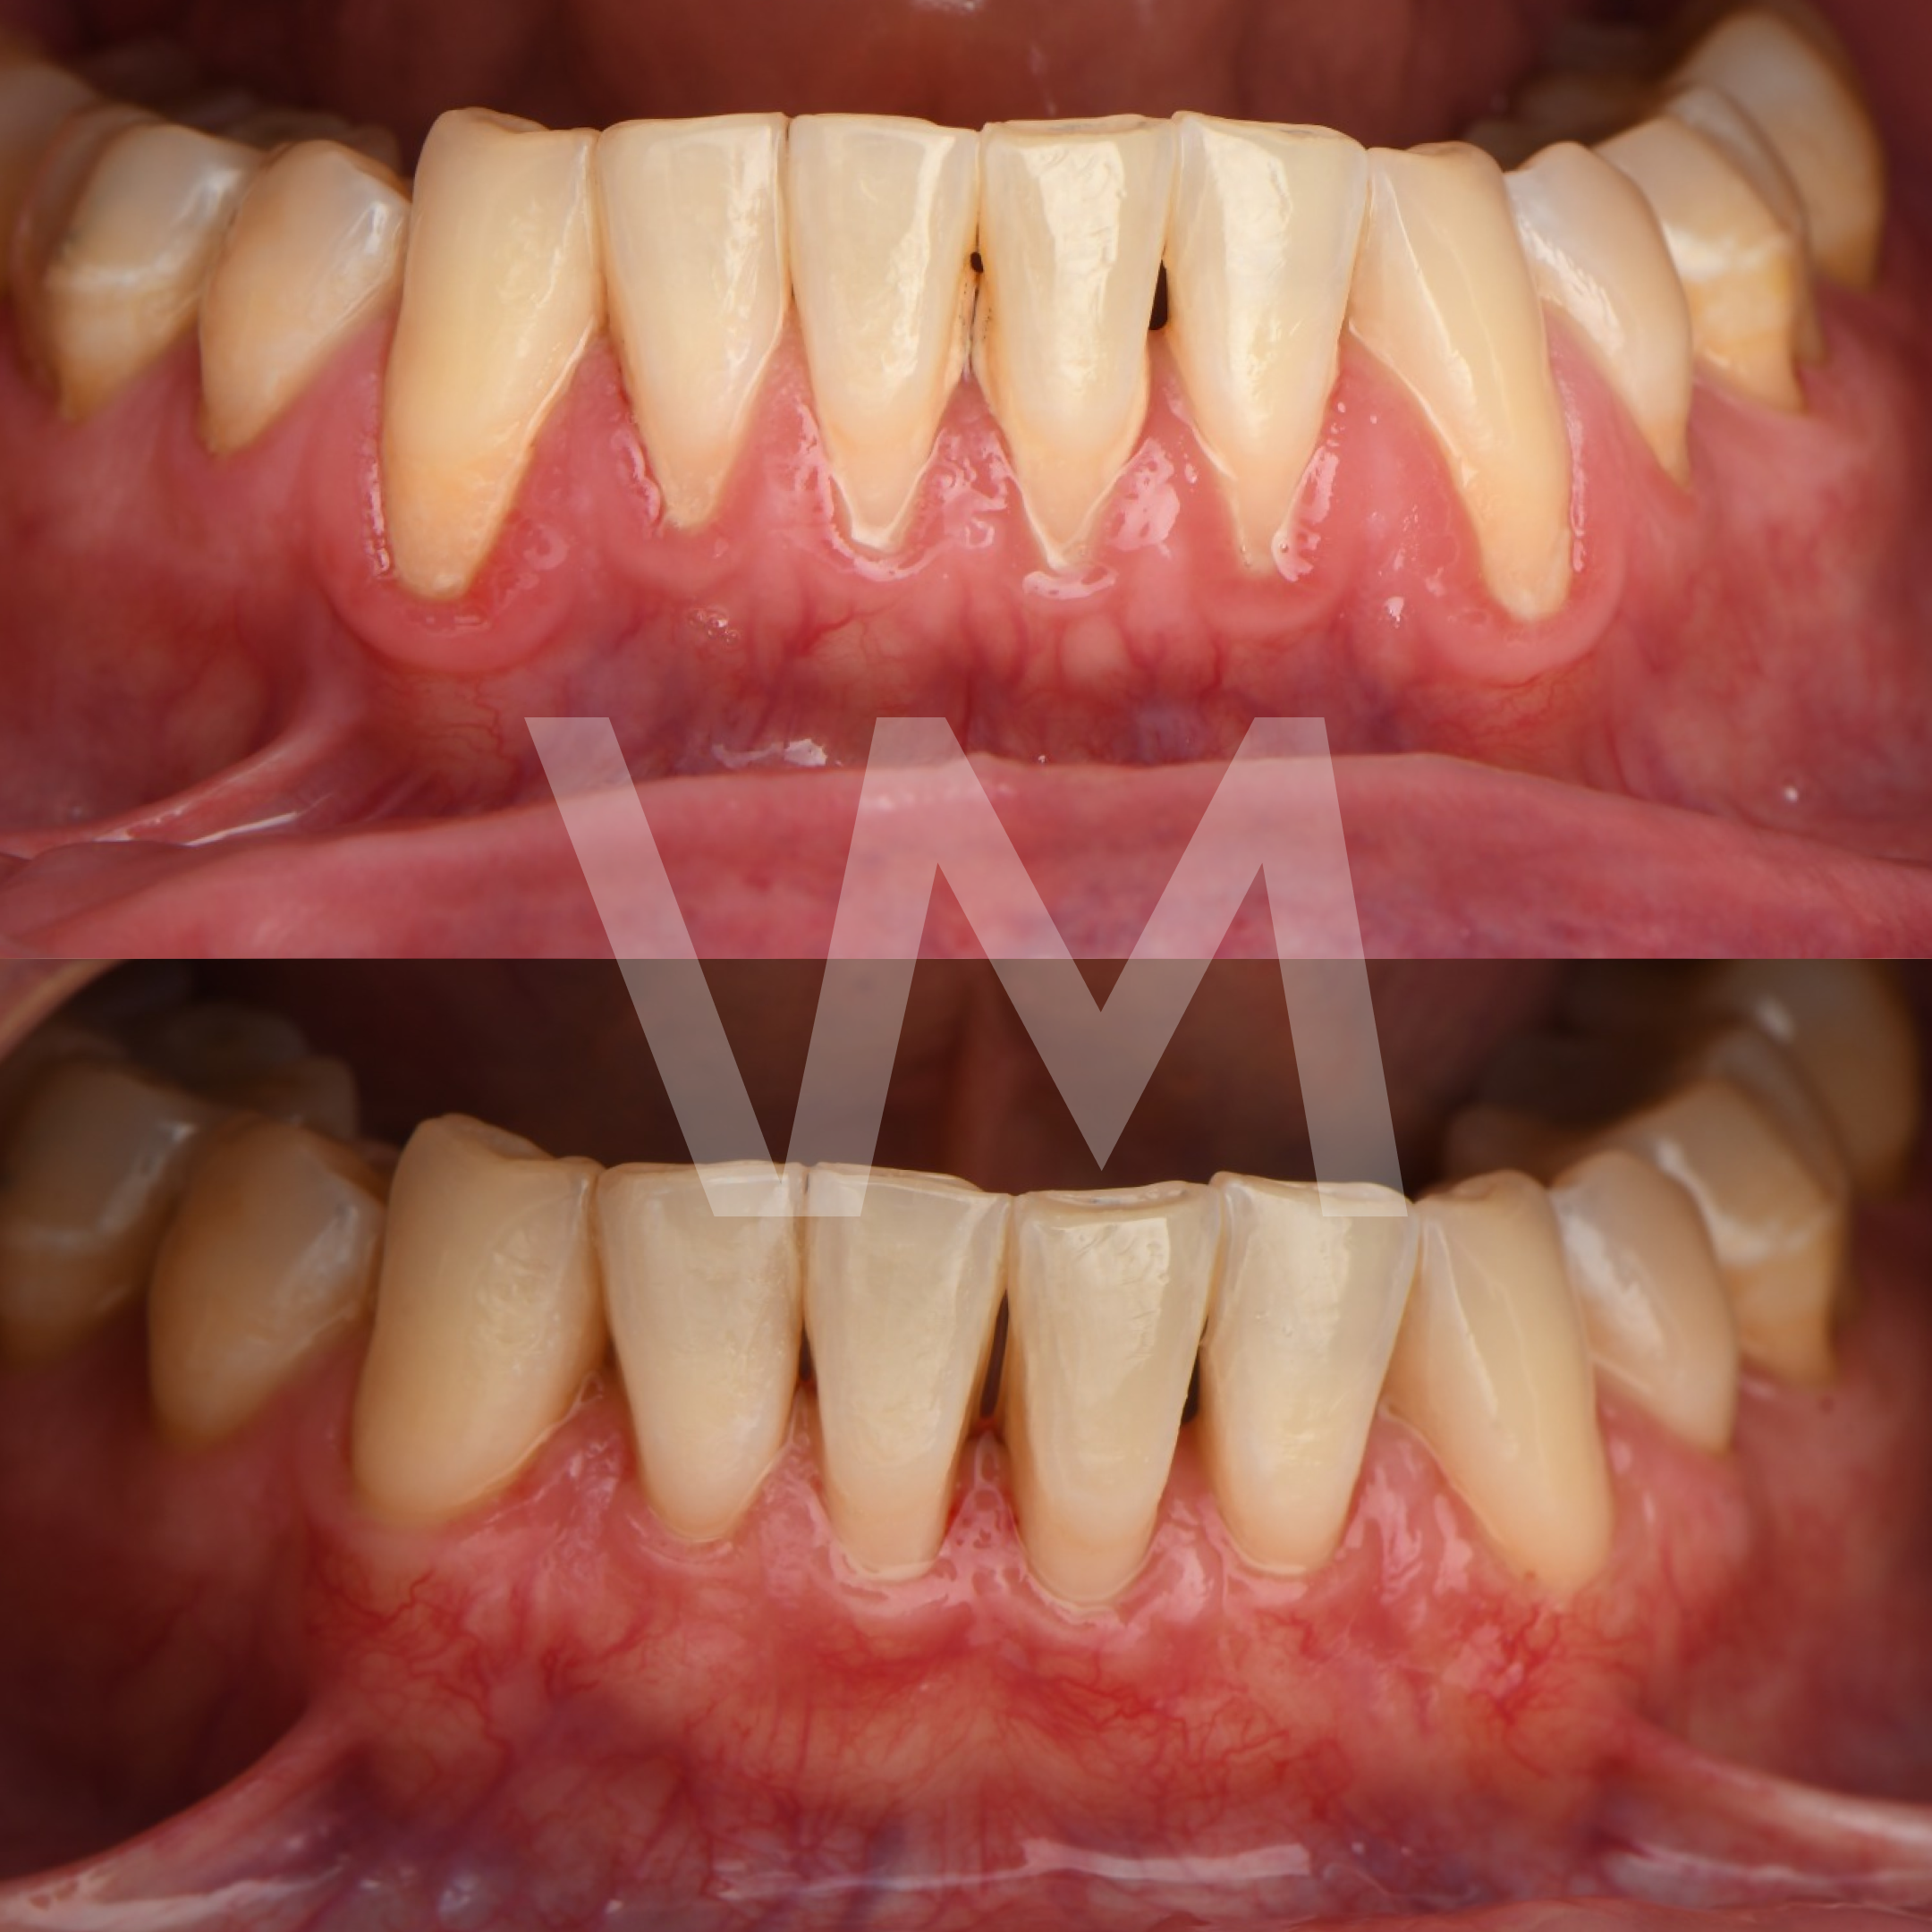

Cirugías de Injertos de Encía del Paladar e Injertos Sintéticos para el Tratamiento de Recesiones Gingivales

Las recesiones gingivales son un problema común en el que las encías retroceden, dejando expuesta la raíz del diente y aumentando el riesgo de sensibilidad dental, deterioro del hueso y pérdida de dientes. Para corregir estas recesiones y restaurar la salud gingival, se pueden realizar cirugías de injertos de encía del paladar e injertos sintéticos.

- Mejora la salud gingival y previene la progresión de la recesión gingival.

- Reduce la sensibilidad dental causada por la exposición de la raíz del diente.

- Mejora la estética de la sonrisa al restaurar el contorno gingival natural.

Casos clínicos realizados por la Dra. Paulina